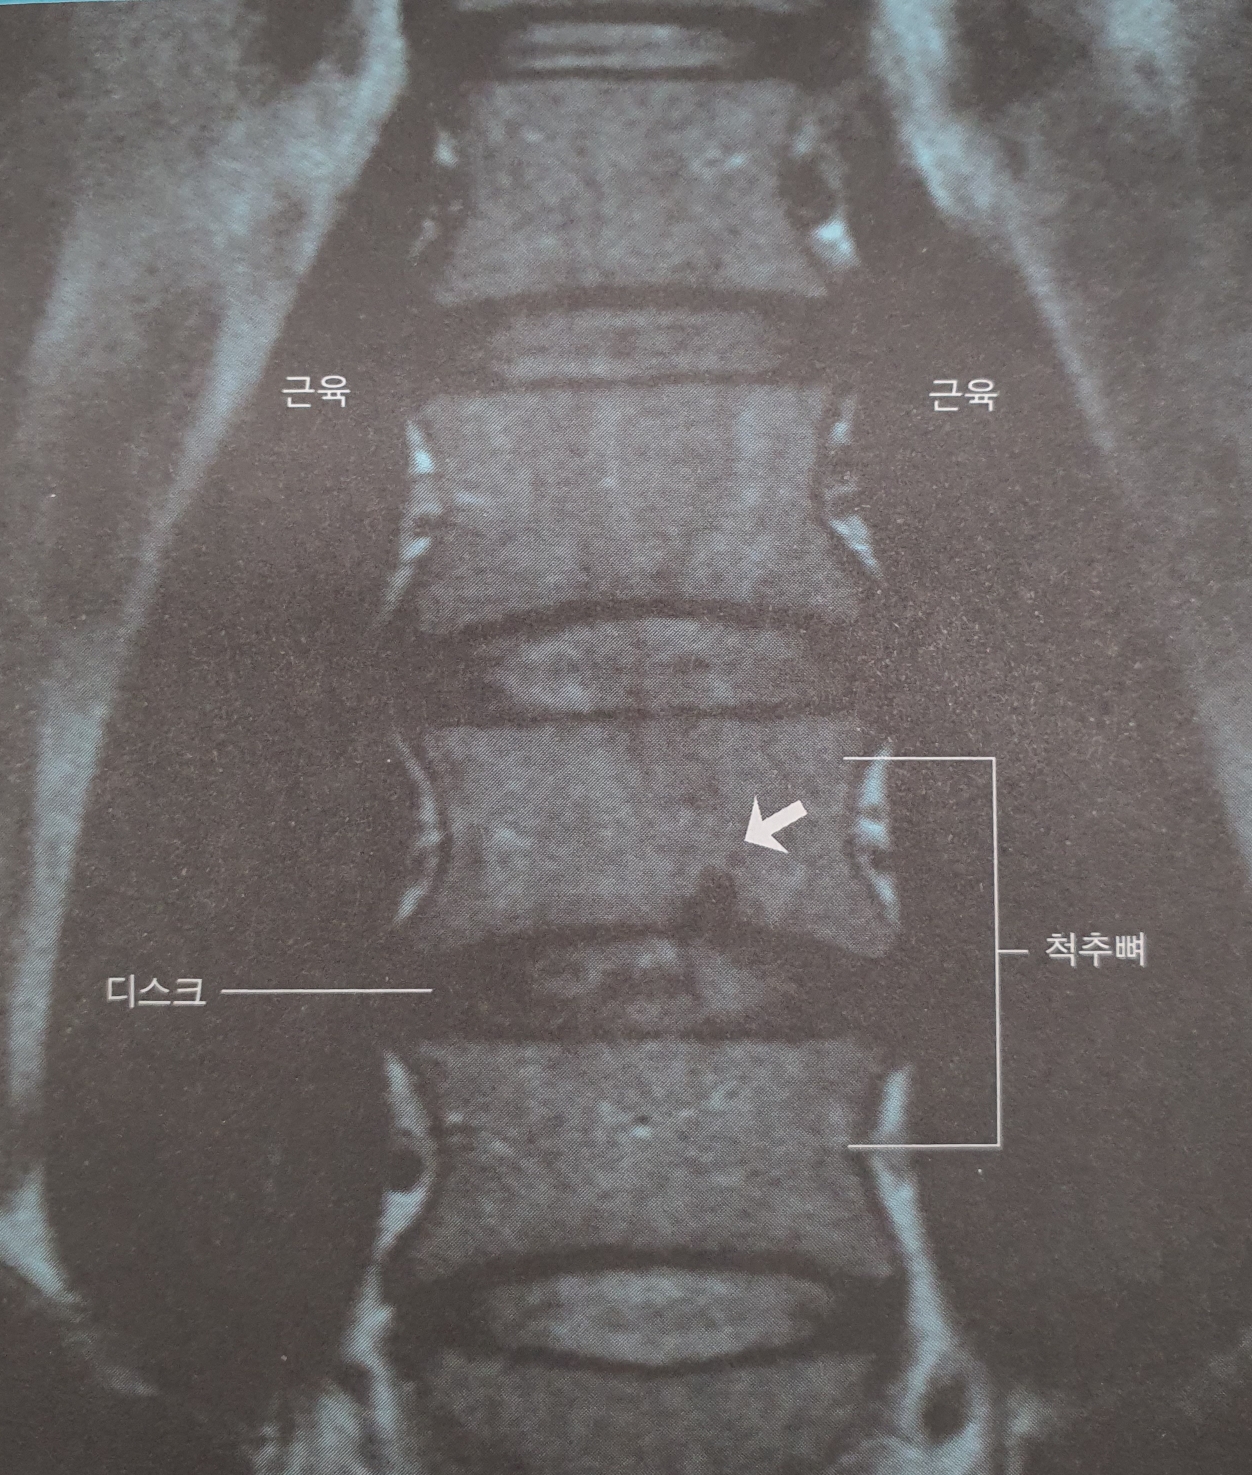

그림 디스크 모양

디스크는 수핵이라는 앙금미 든 참쌀떡이다.

그림 디스크 손상

디스크 손상 3가지

- 종판 손상, 섬유륜 손상, 디스크 탈출

그림 2.8